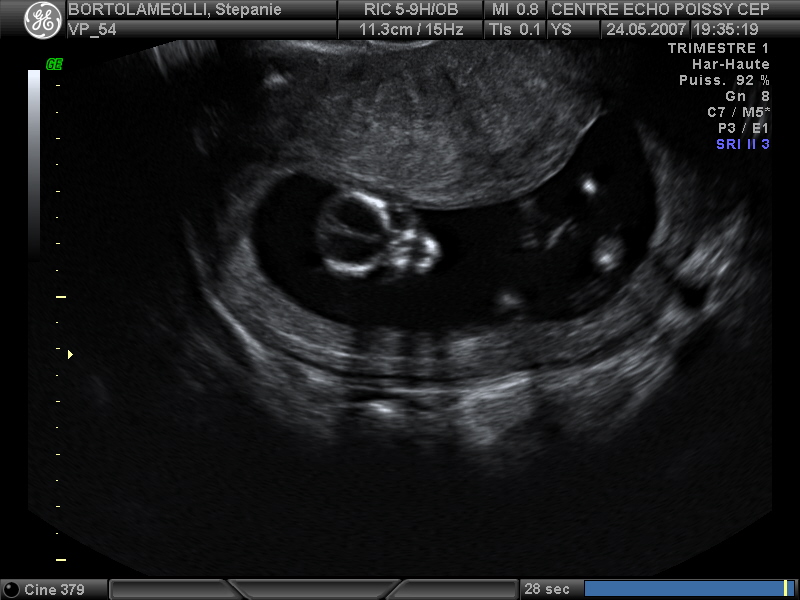

Echographies

Mai 2007